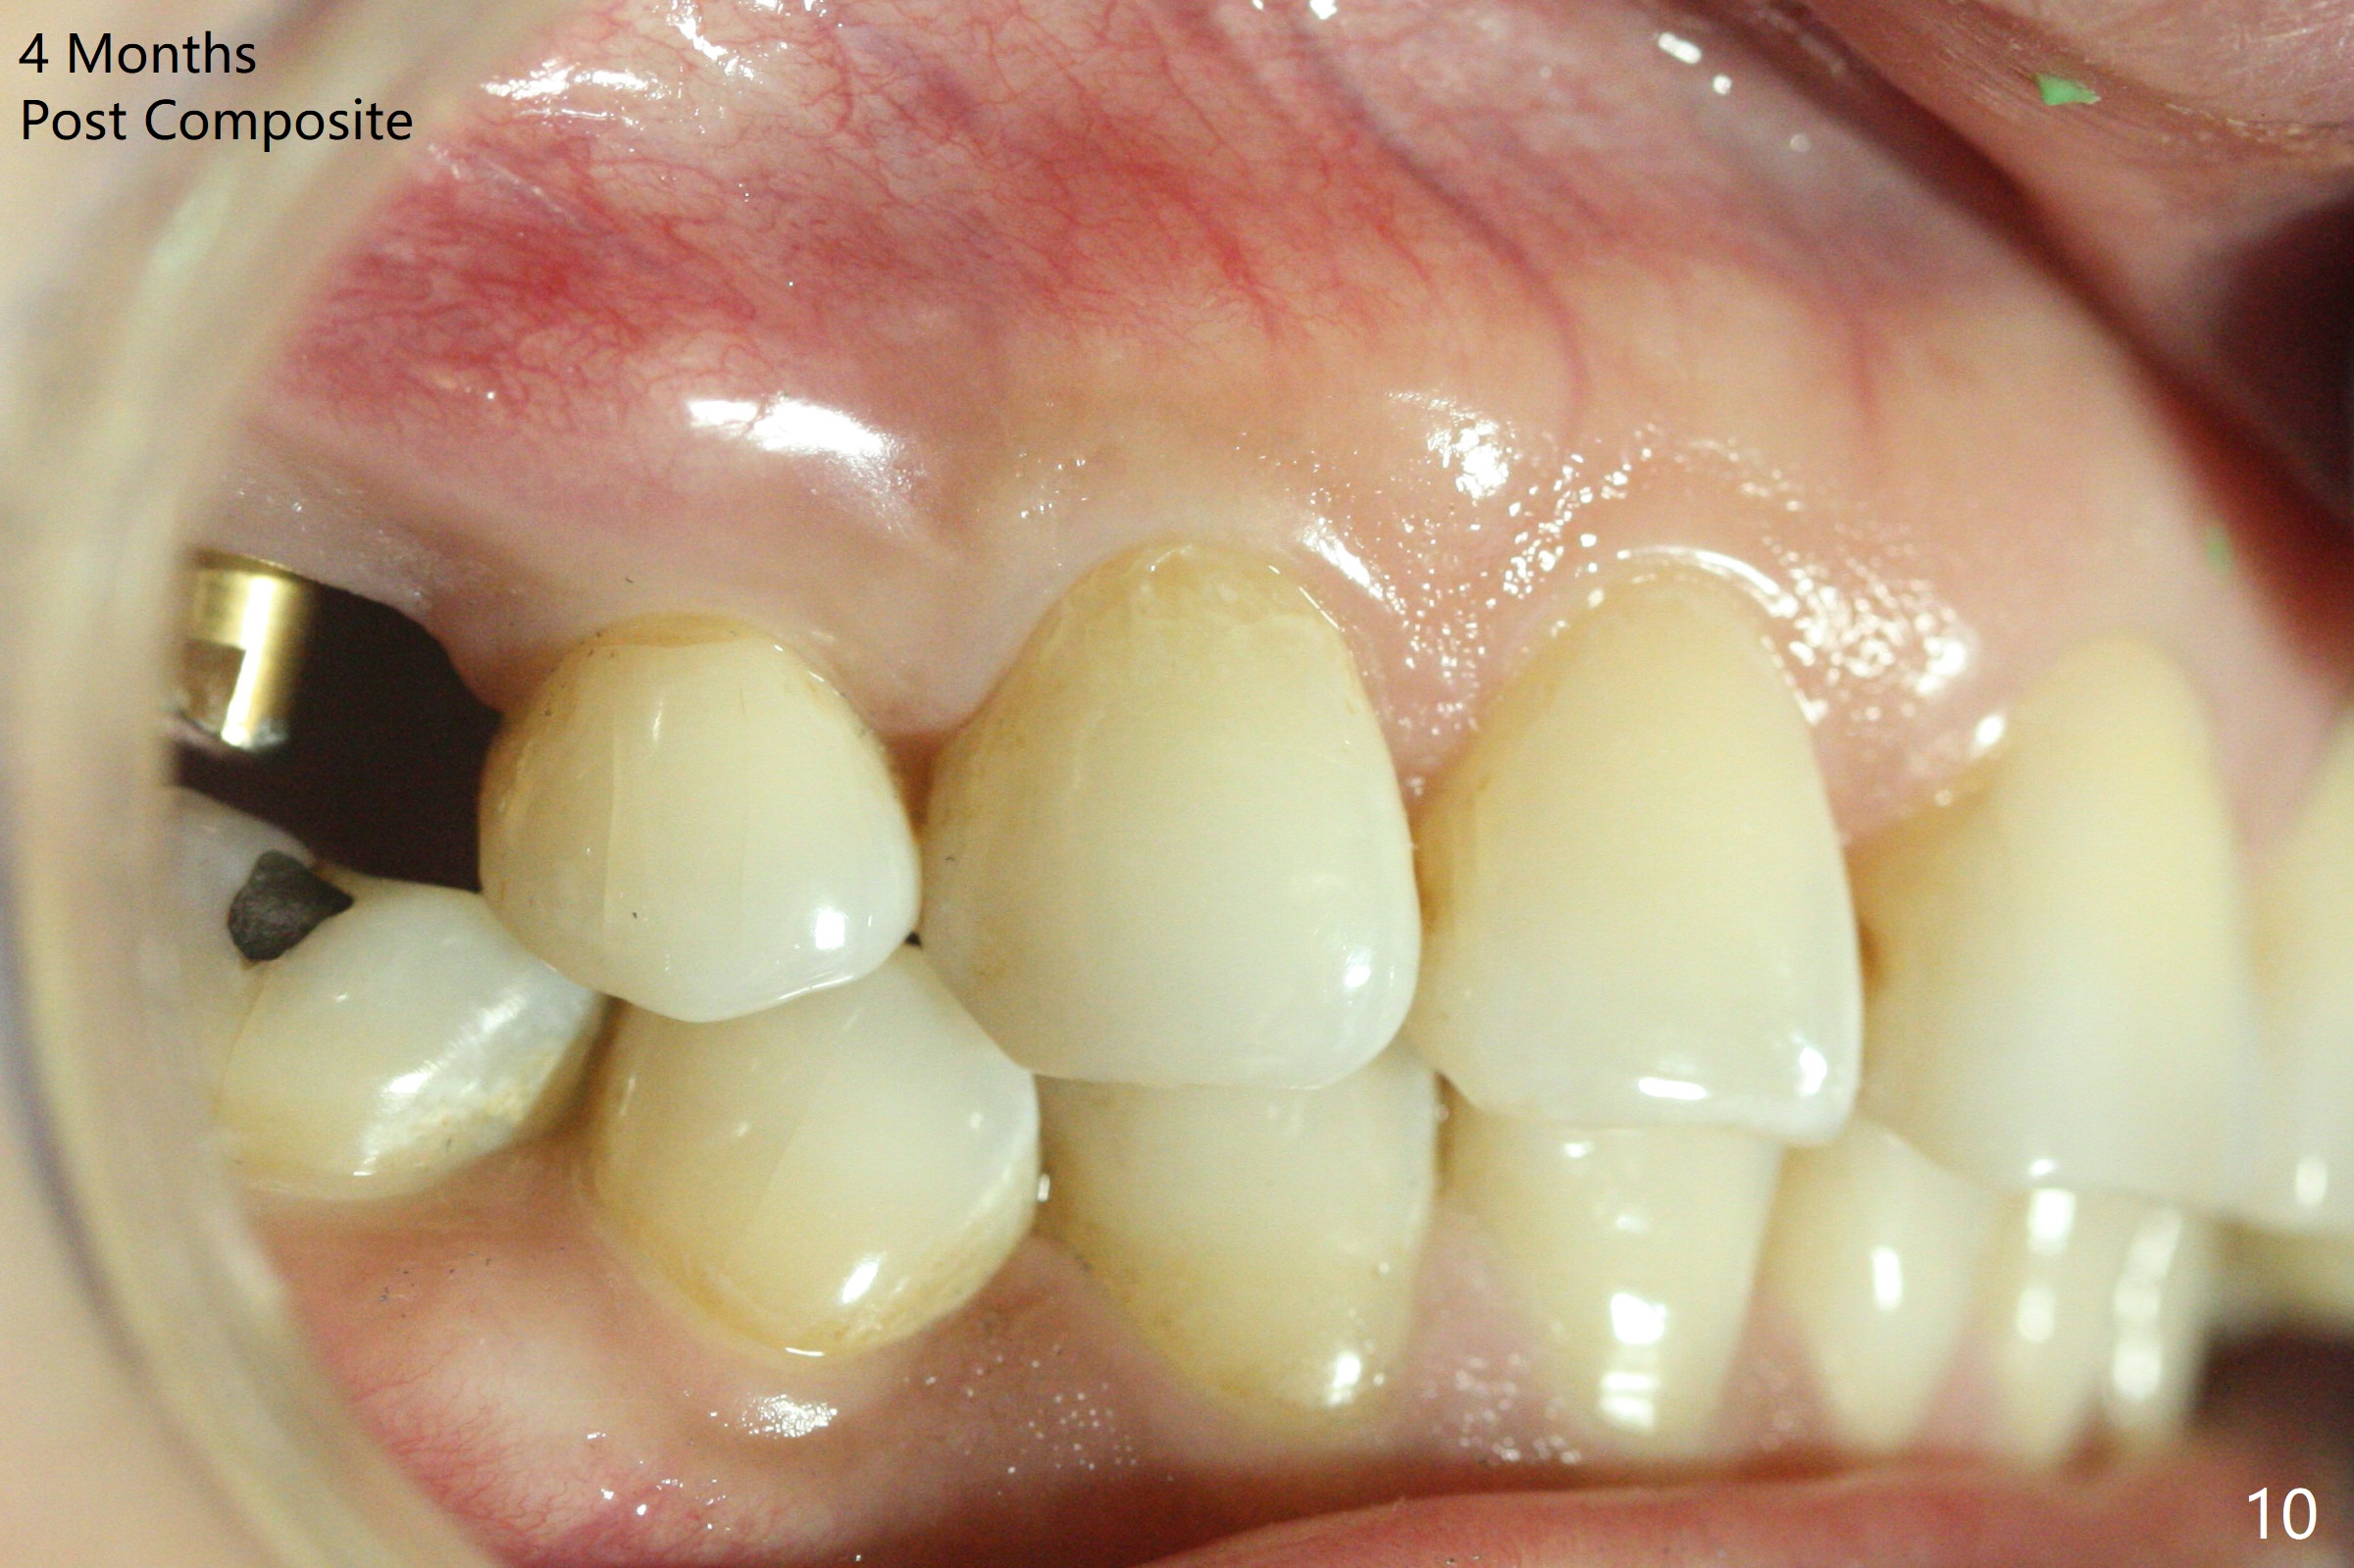

A 36-year-old woman (after #3 immediate implant and #31 socket preservation) wants to take care of the discolored canine 20 years post orthodontic treatment with extraction (Fig.1-3). RCT (Fig.4) appears to whiten the tooth (Fig.5 (A4)). The darkness appears to rebound 1 month post RCT, after removal of Gutta Percha for take home internal and external bleaching (Fig.6). The patient returns for composite after 3-week whitening (Fig.7,8). The shades of composite are bleach (flowable, C1) and B1 (packable, C2, Fig.9). The shade of the RCT tooth is compatible with that of the neighboring teeth 4 months post composite (Fig.10) when the implant at #3 has a new abutment.